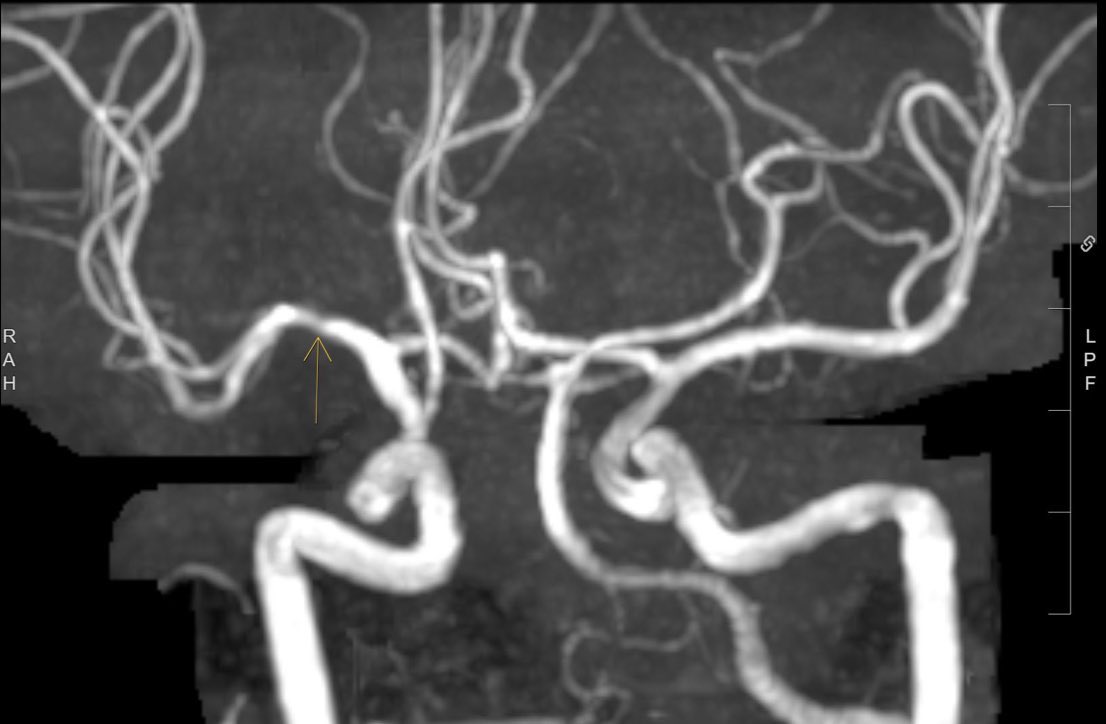

Not every intracerebral hemorrhage needs a CTA